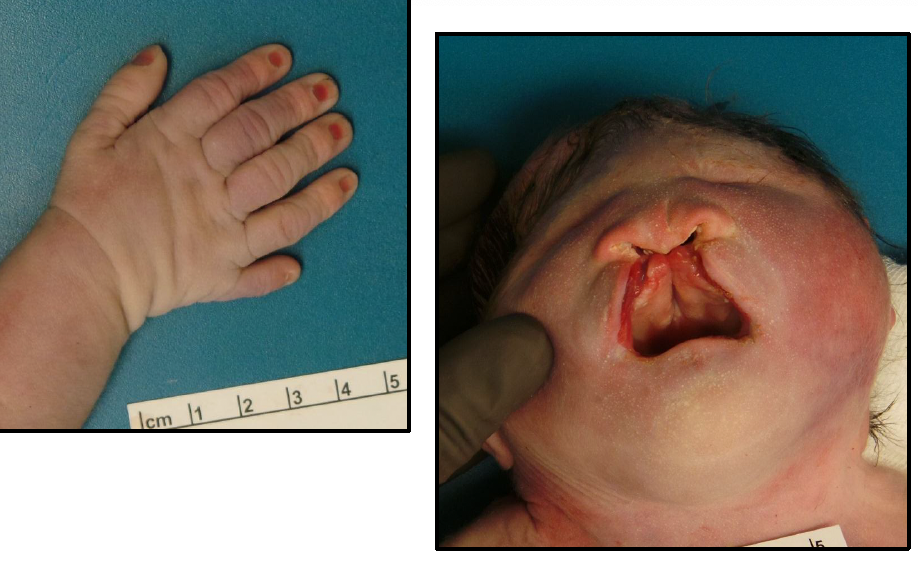

trisomy 13 - patau syndrome

microcephaly

mental retardation

microphthalmia

polydactyly

cardiac defects

umbilical hernia

renal defects

cleft lip/palate

rocker bottom feet

**majority die in utero

cleft palate

high arch